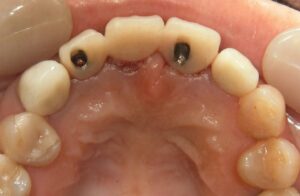

症例写真

before

after1

after2

| 施術名 | 抜歯即時荷重 |

| 施術の説明 | 歯を抜歯してすぐにインプラントを埋入し、そのインプラントに仮歯を装着する治療方法 |

| 施術の副作用 | 噛んでしまうことで骨とインプラントの結合が不十分になる可能性があり、インプラントの安定性に問題が生じることがあります。十分な検討と適切なアフターケアーが必要です。 |

| 施術の価格 | 495,000円(税込)×2 ポンティック 110,000円(税込) ※2本でブリッジ+ポンティックのケース |